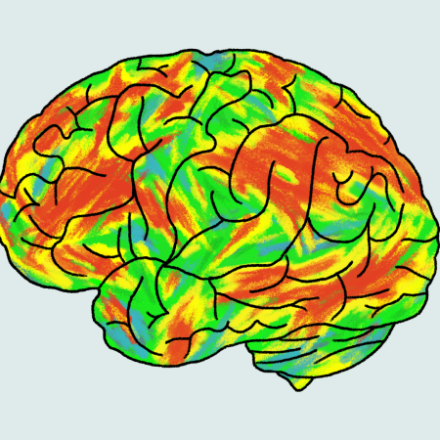

What experts say about taking psilocybin as an alternative treatment for depression